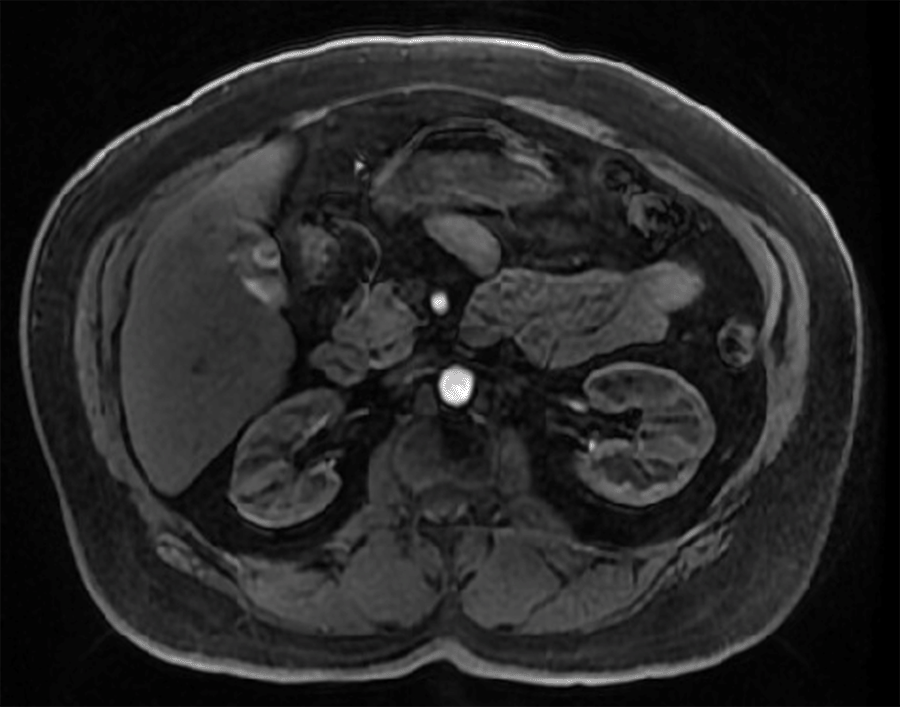

The lesion was described as a well-defined hypervascular mass on CAT scan in our patient. At the same time, on MRI, the pre-T1 series showed a lesion partially obscured by particulate within the gallbladder. T2-imaging showed a well-defined, briskly enhancing mass inseparable from the gallbladder wall with associated bulging (Figure 3). Other case reports have described paragangliomas as homogenous or heterogeneous soft-tissue masses with increased enhancement due to hypervascularity on CT imaging and low to intermediate signal intensity on MRI T1-weighted images, in contrast to the high-intensity signaling seen on T2-weighted images.16

Figure 3. Pre-T1 Series Axial 3D LAVA Phase of Well-Defined Gallbladder Mass, Inseparable from Gallbladder Wall. Published with Permission